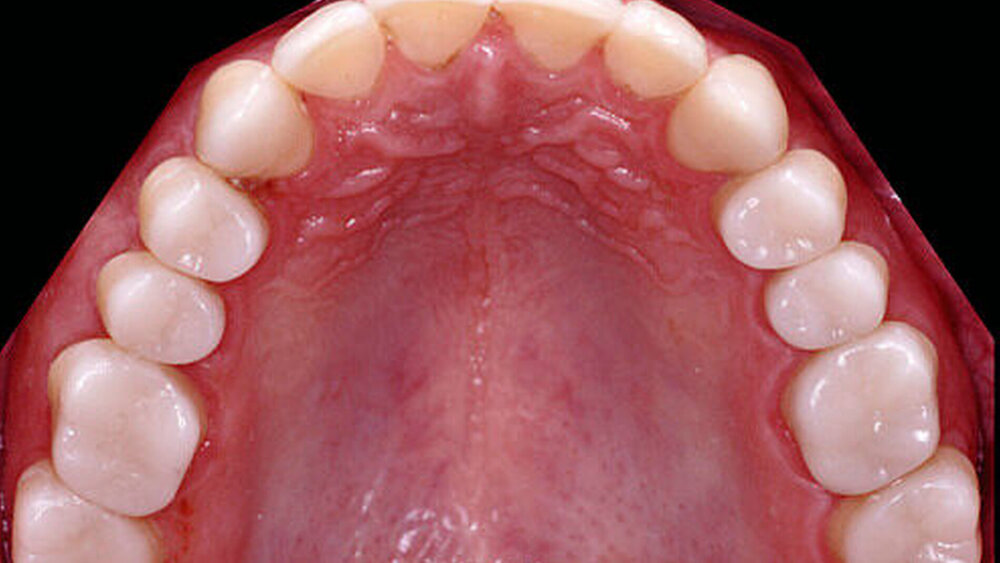

Wird die Bisslage vom Patienten beschwerdefrei akzeptiert, kann die Übertragung der Situation entweder direkt in vollkeramische Restaurationen oder zunächst in CAD/CAM-gefräste, langzeitprovisorische Repositions-Veneers oder -Onlays aus Hochleistungs- polymer – meist PMMA-Material – erfolgen (Abbildung 4). Für die Konstruktion können die Datensätze der Wax-up-Modelle verwendet werden. Die Table Tops werden gewöhnlich mittels Adhäsivtechnik auf natürlichen Zähnen und Kunststofffüllungen befestigt, können allerdings auch bei entsprechender Vorbehandlung (intra-orales Anstrahlen) auf metallischen und keramischen Restaurationsoberflächen eingesetzt werden [Bertolotti et al., 1994]. Da die neue Bisssituation nun permanent inkorporiert ist, können sich die neuronalen Bewegungsmuster besser adaptieren. Um künftig funktionelle Beschwerden nach definitiver Rekonstruktion der vertikalen Kieferrelation möglichst auszuschließen, sollte diese semipermanente Phase für etwa sechs bis zwölf Monate beibehalten werden.